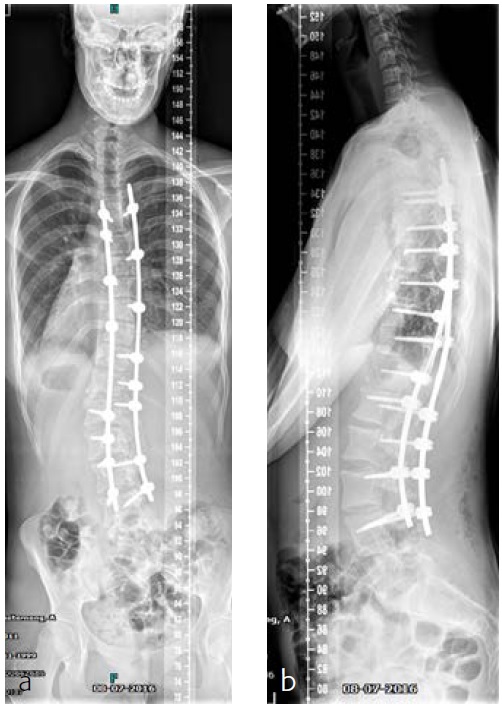

After her visit to our clinic, she was planned for surgical correction of the deformity from T5L4 (Fig 11). Surgical procedure with IONM (TC-MEP) postoperative epidural analgesia with the catheter tip at T8. She was mobilised the first postoperative day (Fig 12) and discharged the fourth day after surgery. The patient returned for her 6-month follow-up without any complaints. Limitations are in line with our advice (no sports for 6 months postoperatively). She has no pain and uses no medication.